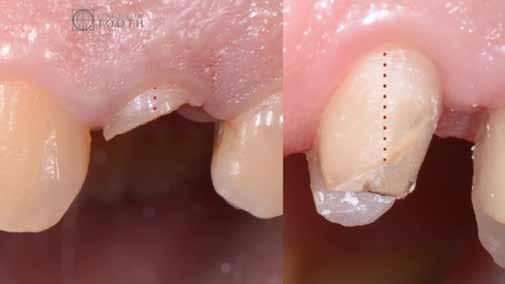

A mindennapi gyakorlatban gyakran találkozunk súlyos fogszuvasodással. A fogorvosnak mindig kihívást jelent a döntés, hogy kihúzzuk és implantátummal pótoljuk, vagy megmentjük a fogat, de kétséges a hosszú távú prognózis. Számos cikkből tudjuk, mint például Seltzer és Kim (Comparison of Long term survival of implant and endodontically treated teeth J Dent Res 93(1):19-26, 2014) cikke, hogy a fogak viszszanyerése jobb megoldás, különösen a fiatalabb betegeknél. A kirakós hiányzó kulcsa az általános fogorvos számára gyakran a maradó fogazat jó biomechanikai értékelése. Az endodontikusan kezelt fogak kudarcainak többsége valójában mechanikai hibákhoz, például repedéshez és töréshez kapcsolódik. A maradó fogszerkezet gondos biomechanikai értékelése, valamint a mechanikai teljesítményt javító technikákra való összpontosítás a legfontosabb a hosszú távú eredmény keresésében. A szerző praxisában a vertikális pre-

parálás és a minimális megközelítés kombinációja, valamint az ortodontikus extrúzió alkalmazása a restauratív fogászatban megváltoztatja a helyzetet, amint azt a következő eset is mutatja.

Egy 35 éves kaukázusi férfi páciens az 1.4-es fog (felső első premoláris) törése miatt kereste fel rendelőnket, a törés ferde volt. A sérült fogak helyreállítása során az egyik legfontosabb lépés a megmaradt fogazat biomechanikai értékelése . Egy hiba ebben a fázisban káros a hosszú távú eredményre . A legtöbb repedést például a fogüregek helyreállító fogászathoz való helytelen előkészítése okozza. Ugyanígy a fennmaradó szerkezet helytelen értékelése idővel mechanikai okokból bekövetkező meghibásodáshoz vezethet.

2. ábra: Az okkluzális nézet a fogszerkezet mennyiségét mutatja, a röntgenfelvételen az 1.5. fogon II. osztályú szuvasodás is látható. Még ha lehetséges is ezeket az eseteket koronahosszabbítással kezelni, a végeredmény átlagosan nem kielégítő. A ferrule gyógyulása korlátozott, és olyan parodontális szövődményekkel is találkozunk, mint a fekete háromszögek, a szomszédos fogak gyökérkitettsége. A fogszabályozó extrúzió sokkal előnyösebb.

7. ábra: A bukkális szerkezet összehasonlítása extrudálás előtt/után . A maradék fogazati struktúra okklusális terhelése most sokkal kedvezőbb a hosszú távú eredmény szempontjából .